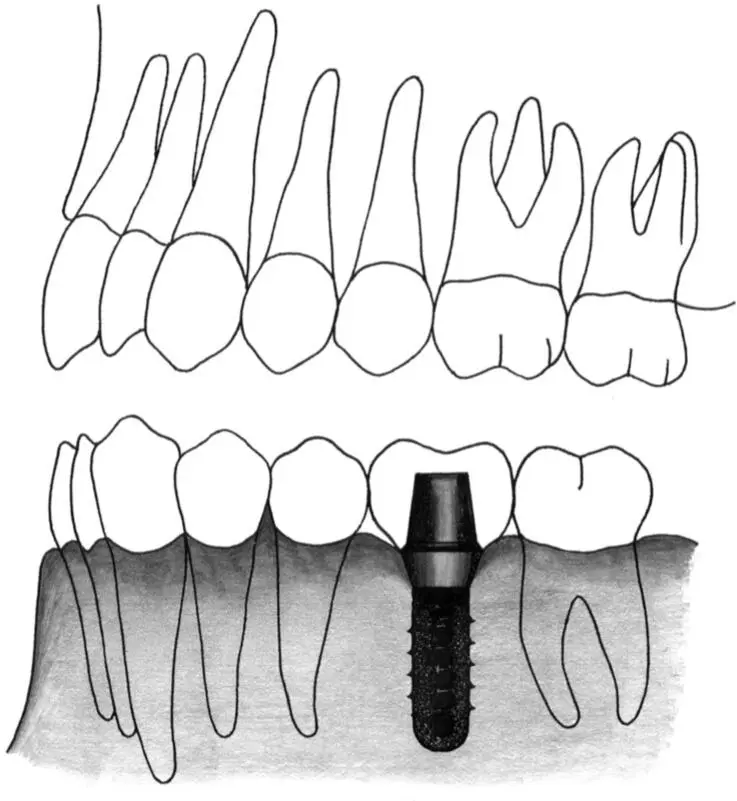

Figs 1-11k and 1-11l Occlusal (k) and lateral (l) views of a short distal extension situation. A regular neck implant is indicated to restore the missing first molar and serve as a distal abutment to a combined tooth- and implant-supported three-unit fixed partial denture. The implant is positioned 11 to 12 mm from the tooth.